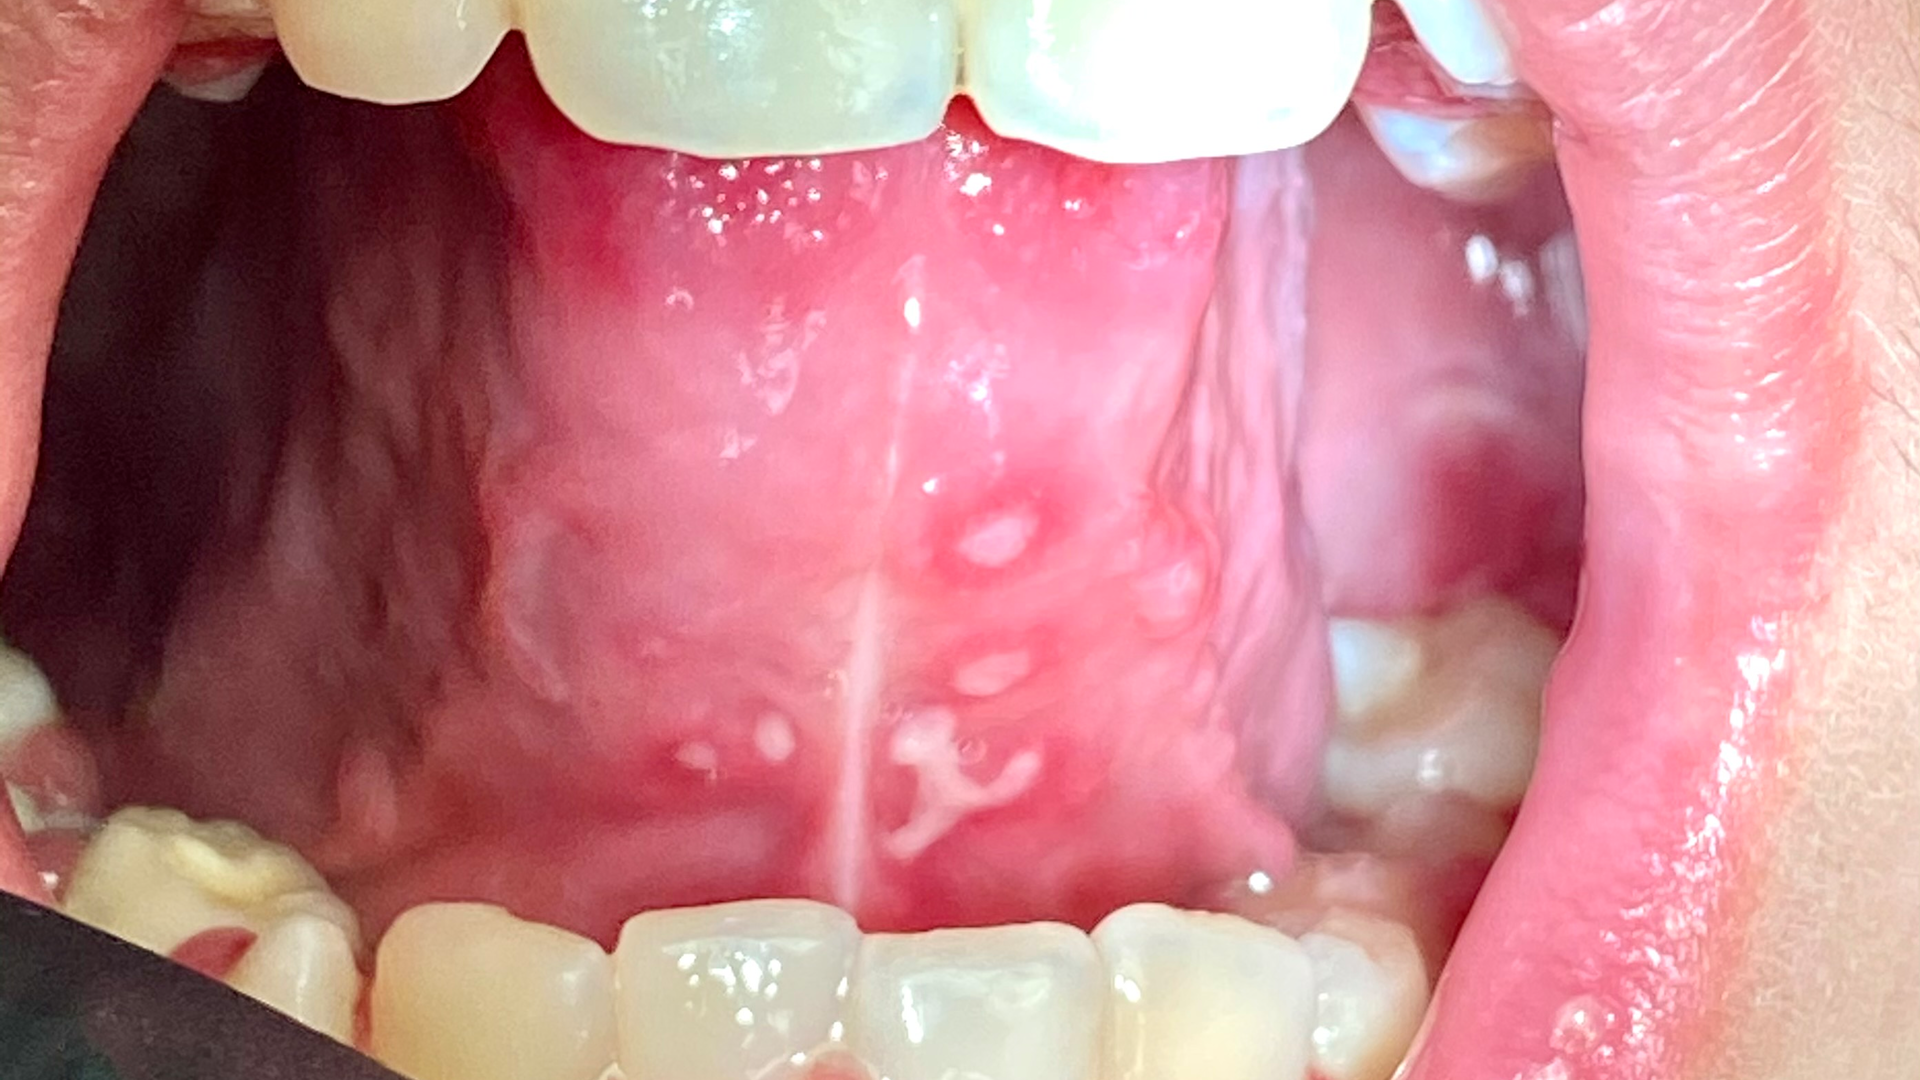

Note: The pictures are not of the highest quality as the patient was in extreme discomfort when I took them.

Definitive diagnosis is likely one of two: Herpangina or acute primary herpetic gingivostomatitis

The saying “nothing is for certain unless it’s in a petri dish” stands true in all pathology cases, including this one. However, based on the symptoms and clinical presentation, I was able to surmise that it was more than likely either herpangina or APHG, although I’m leaning toward APHG.